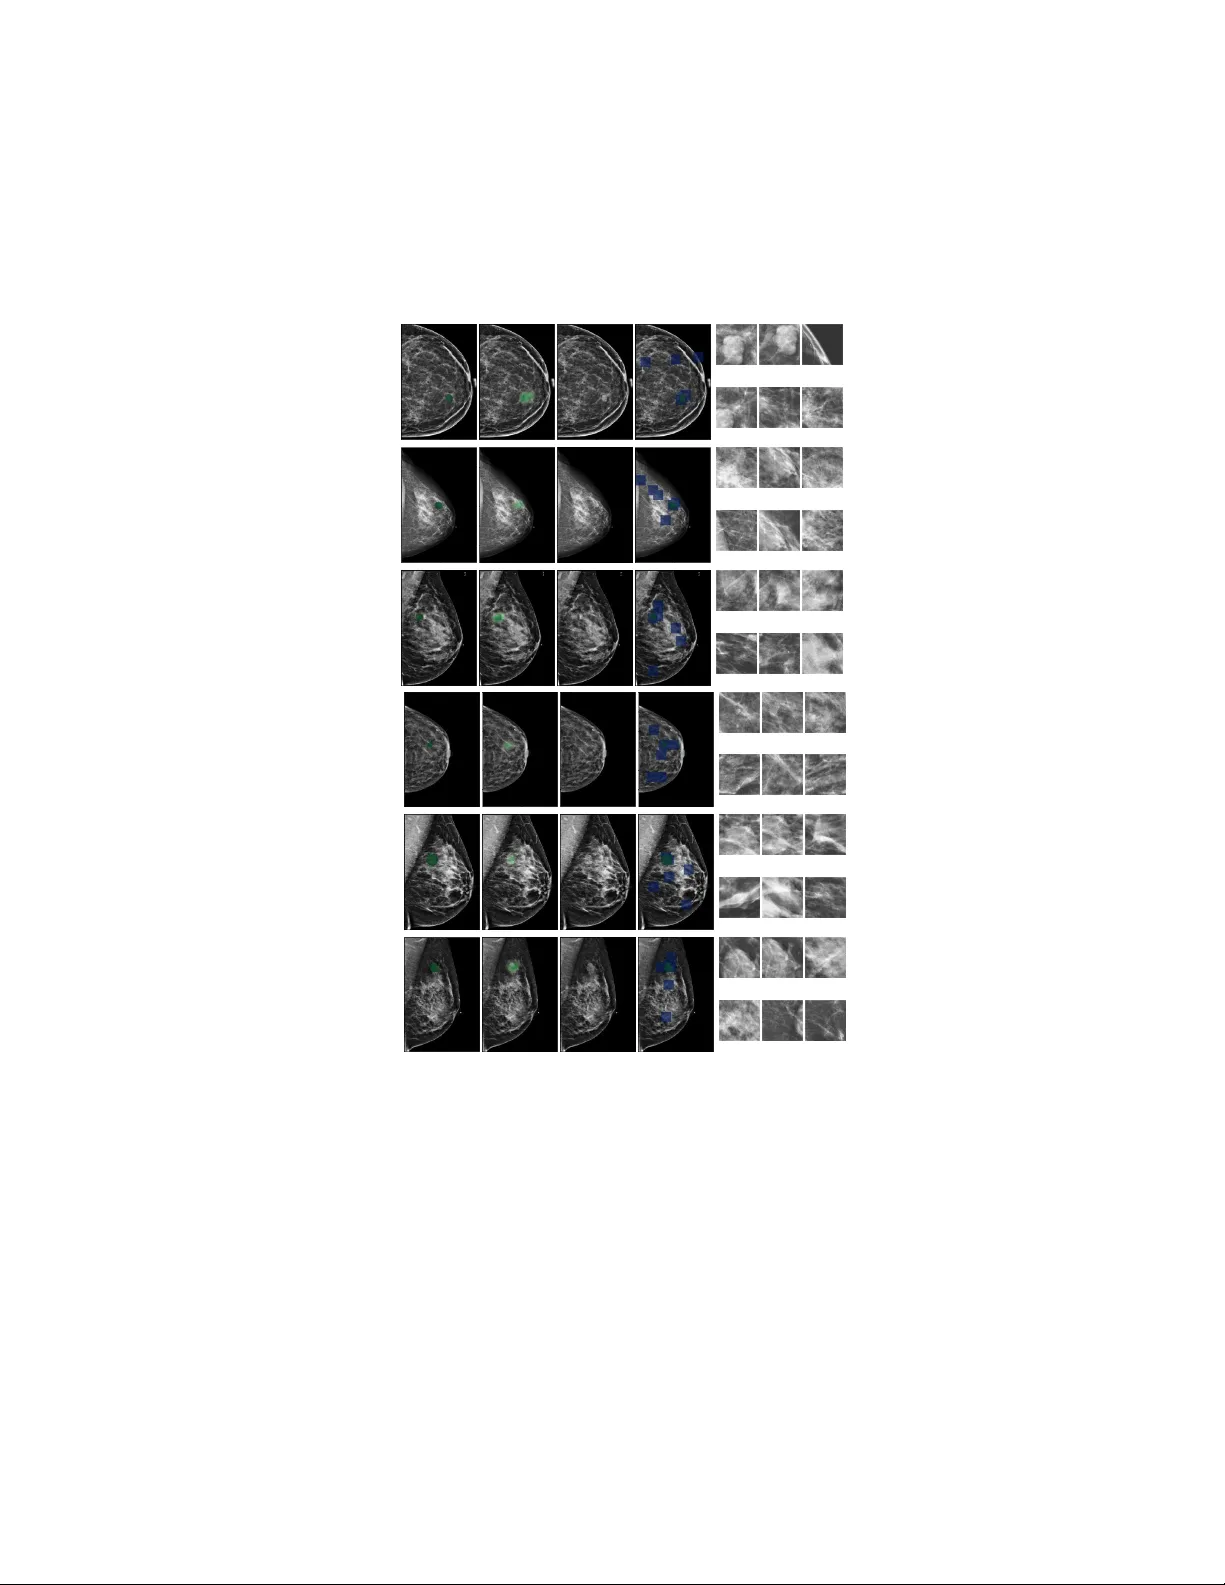

본 논문은 유방암 스크리닝을 위한 새로운 딥러닝 프레임워크인 Globally‑Aware Multiple Instance Classifier(GMIC)를 제안한다. 기존의 의료 영상 분석 모델은 자연 이미지와 달리 고해상도와 작은 병변이라는 특성 때문에 메모리 제한과 정보 손실 문제가 있었다. 이를 해결하기 위해 저자들은 세 가지 핵심 모듈로 구성된 아키텍처를 설계하였다. 첫 번째 로컬라이제이션 모듈은 ResNet‑22를 경량화하여 전체 해상도(2944×1920) 이미지를 직접 입력한다. 마지막 residual block의 피처맵을 1×1 컨볼루션과 시그모이드 활성화로 변환해 클래스별 살리언시 맵 A를 생성한다. 이 맵은 각 픽셀의 클래스 기여도를 나타내며, 전역적인 조직 분포와 미세 병변을 동시에 포착한다. 두 번째 디텍션 모듈은 살리언시 맵 A를 기반으로 K(=6)개의 ROI 패치를 선택한다. 알고리즘 1은 A를 정규화하고, 상위 t% 영역을 탐색해 평균 점수가 가장 높은 256×256 크기의 패치를 순차적으로 추출한다. 추출된 패치는 겹치지 않도록 마스크를 초기화해 중복을 방지한다. 이렇게 얻은 고해상도 패치는 작은 석회화나 미세 종양과 같은 작은 병변을 상세히 분석할 수 있게 한다. 세 번째 MIL 모듈은 각 패치를 ResNet‑18(사전학습)으로 임베딩해 128‑차원 피처 h̃_k를 만든 뒤, 게이트형 어텐션 메커니즘을 적용한다. 어텐션 가중치 α_k는 패치별 중요도를 학습적으로 추정하며, 가중합 z=∑α_k h̃_k를 최종 분류기에 전달한다. 시그모이드 활성화와 가중치 w_mil을 사용해 이미지‑레벨 예측 ŷ_mil을 산출한다. 학습 과정에서 디텍션 모듈은 비미분 가능하므로, 로컬라이제이션 모듈과 MIL 모듈을 별도 손실로 결합한다. 전역 예측 ŷ_loc은 살리언시 맵 A에 대해 상위 t% 영역 평균을 취한 소프트 풀링 f_agg(A)로 계산하고, BCE 손실을 적용한다. 또한 A에 L_reg=∑|A_ij|^β 정규화를 부여해 과도한 활성화를 억제한다. 최종 손실은 클래스별 BCE(ŷ_loc, y)+BCE(ŷ_mil, y)+λ·L_reg 형태이며, 두 예측을 평균해 최종 추론값 ŷ=(ŷ_loc+ŷ_mil)/2로 만든다. 실험에서는 뉴욕대 의료 데이터베이스에서 229,426개의 검진(1,001,093 이미지)을 사용했다. 데이터는 학습 186,816, 검증 28,462, 테스트 14,148로 분할했으며, 양성·악성 라벨을 균형 있게 샘플링했다. 하이퍼파라미터는 로그 스케일의 랜덤 서치를 100번 수행해 최적화했으며, Adam 옵티마이저와 40 epoch 학습을 적용했다. 성능 평가 결과, GMIC는 악성 판별에서 AUC 0.900, 양성(악성·양성 모두)에서 0.784를 기록했으며, ResNet‑22 베이스라인(악성 0.827, 양성 0.731)보다 현저히 우수했다. 어텐션을 제거한 GMIC‑noattn은 성능이 감소해 어텐션 메커니즘이 핵심임을 확인했다. 무작위 패치를 이용한 GMIC‑random은 MIL만 사용했을 때보다 낮은 성능을 보이며, 전역 살리언시 맵과 로컬 패치 정보를 결합한 것이 성능 향상의 주된 요인임을 입증했다. 임상적 가치 평가를 위해 14명의 방사선 전문의와 동일한 720건(1440 유방) 검진에 대해 독자 연구를 진행했으며, GMIC 앙상블 모델은 AUC 0.876으로 평균 방사선 전문의(0.778)와 최고 전문의(0.860) 모두를 능가했다. 인간·기계 하이브리드(예측 평균) 역시 0.883의 AUC를 기록해 상호 보완적임을 시사한다. Localization 측면에서는 픽셀‑레벨 세그멘테이션(전체 데이터의 <1%)을 이용해 연속형 F1 점수를 계산했으며, 악성 0.207, 양성 0.133을 얻었다. 시각화 결과, 살리언시 맵은 실제 병변에 높은 활성화를 보였으며, 어텐션 가중치가 높은 패치가 병변 영역과 겹치는 것을 확인했다. 다만 큰 병변의 경우 고정된 t% 풀링이 일부 영역만 강조하는 한계가 드러났으며, 이는 향후 가변 풀링 전략으로 개선될 수 있다. 결론적으로 GMIC는 고해상도 의료 영상을 전역·국소 정보를 동시에 활용해 강력한 분류 성능과 해석 가능성을 제공한다. 이미지‑레벨 라벨만으로도 픽셀‑레벨 병변 위치를 추정할 수 있어 라벨링 비용을 크게 절감한다. 향후 연구에서는 MIL 모듈의 오류 신호를 로컬라이제이션 모듈에 역전파하는 공동 학습 방식을 도입해 Localization 정확도를 더욱 향상시킬 계획이다.